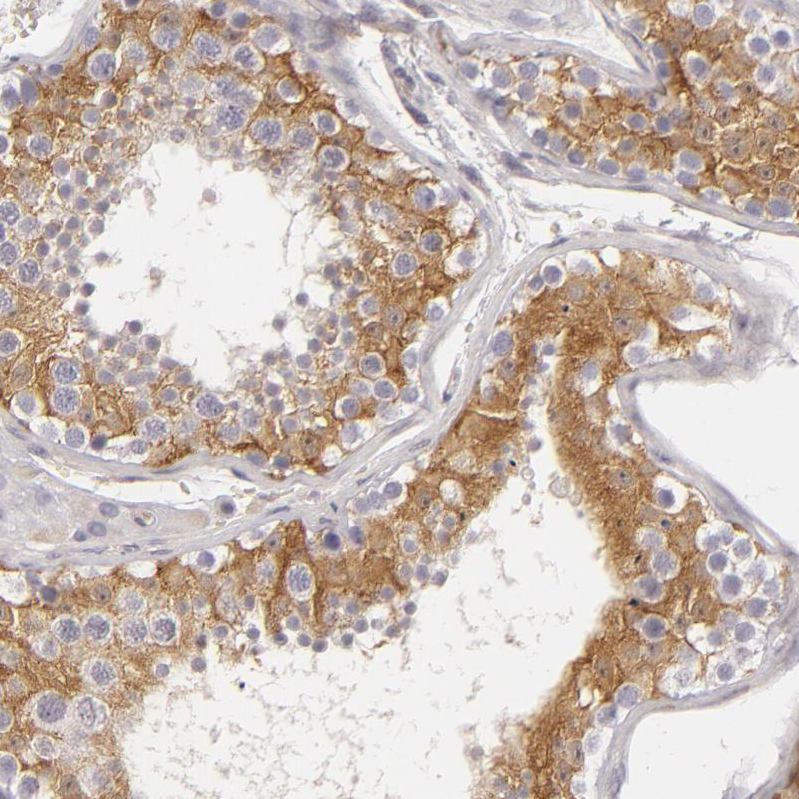

Immunohistochemistry analysis in human lymph node and pancreas tissues using HPA001812 antibody. Corresponding APOBEC3G RNA-seq data are presented for the same tissues.